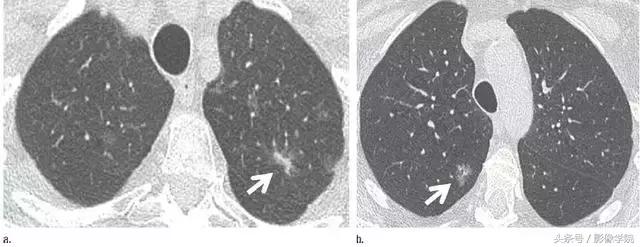

1、错构瘤

图 1 层厚 1 mm 的 CT 横断面图像,(a)为肺窗,(b)为软组织窗,显示边缘平滑、内含脂肪和钙化的实性结节(箭头),符合错构瘤表现。不建议进一步 CT 随访。